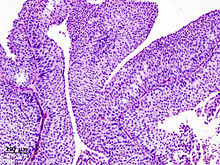

Histopathology of urothelial carcinoma of the urinary bladder. Transurethral biopsy. H&E stain